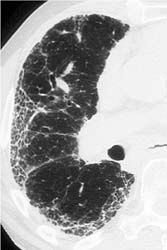

Rheumatoid arthritis, which affects approximately 2.9 million people in Europe, can be difficult to differentiate from other forms of arthritis. Without an early diagnosis, however, it is impossible to assess the true effect of promising early intervention strategies. Could an alternative diagnostic imaging strategy be the answer?